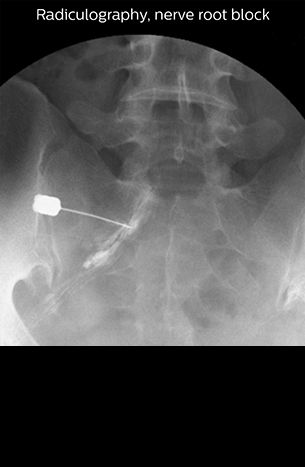

“Before NerveVIEW, diagnosis by MRI alone was sometimes difficult, unless there was a strong suspicion based on clinical symptoms,” says Shoji Yabuki, MD, DMSc, Orthopedic surgeon at Fukushima Medical University School of Medicine. “This is why we routinely perform selective lumbosacral radiculography (nerve root block) and x-ray in such cases. However, radiculography can only depict nerves as far as the contrast agent reaches. When a nerve is distorted by compression, the contrast agent will not pass through this compressed area, preventing us from evaluating the full nerve compression.”

“In such case, we would then browse through axial T2-weighted MR images slice by slice and mentally reconstruct the actual situation based on both radiculography and MRI. Fortunately, NerveVIEW can now very well show nerve courses and presence of nerve compression or edema in one single image series.” “We have often seen NerveVIEW directly depict details of the nerve compression that were not observed by radiculography. Therefore, we think that with NerveVIEW we can reduce the number of invasive examinations, especially for some patients with lumbar plexus symptoms.”

“NerveVIEW can clearly show nerve courses and presence of nerve compression. However, when multiple abnormalities are seen, it can still be hard to determine which nerve is causing the symptoms,” says Dr. Yabuki. “In our experience so far, we see abnormal findings on NerveVIEW in about 70% of elderly patients. As the pain is usually caused by only one nerve, we thus need to find the exact corresponding nerve.” “With a nerve root block, the patient's pain is improved by infiltration of local anesthesia directly around the nerve root considered to be responsible. Knowing such nerve root block findings prior to image interpretation, helps to easily recognize abnormal findings on NerveVIEW as well. In other words, without a priori knowledge, based on symptoms and/or nerve root block findings, we must be aware of the possibility of overdiagnosis.”